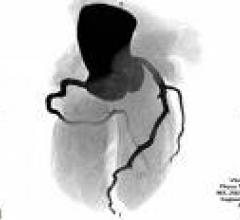

Computed tomography (CT) systems use a series of X-ray images to create an image volume dataset with slices that can be manipulated on any plane using advanced visualization software. The section includes computed tomography scanners, CT contrast agents, CT angiography (CTA and CCTA), CT perfusion, spectral CT (dual-source CT), and iterative reconstruction dose reduction software.

The importance of dealing with the epidemic of coronary artery disease (CAD) is well known, and the tools at our ...

February 2, 2010 - Among noninvasive imaging tests for ruling out coronary artery disease (CAD), computed tomography (CT ...